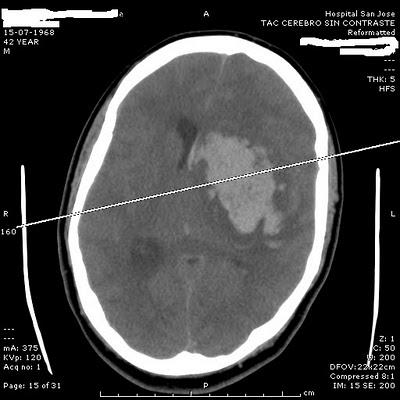

Hoy pudimos conocer por medio del Sofware Synapse,las placas de Rayos y scaner tomado al paciente que confirman el daño cerebral

Puedes ver las placas más abajo.

En el Scaner se aprecia extensa lesión hemorrágica a nivel cerebral